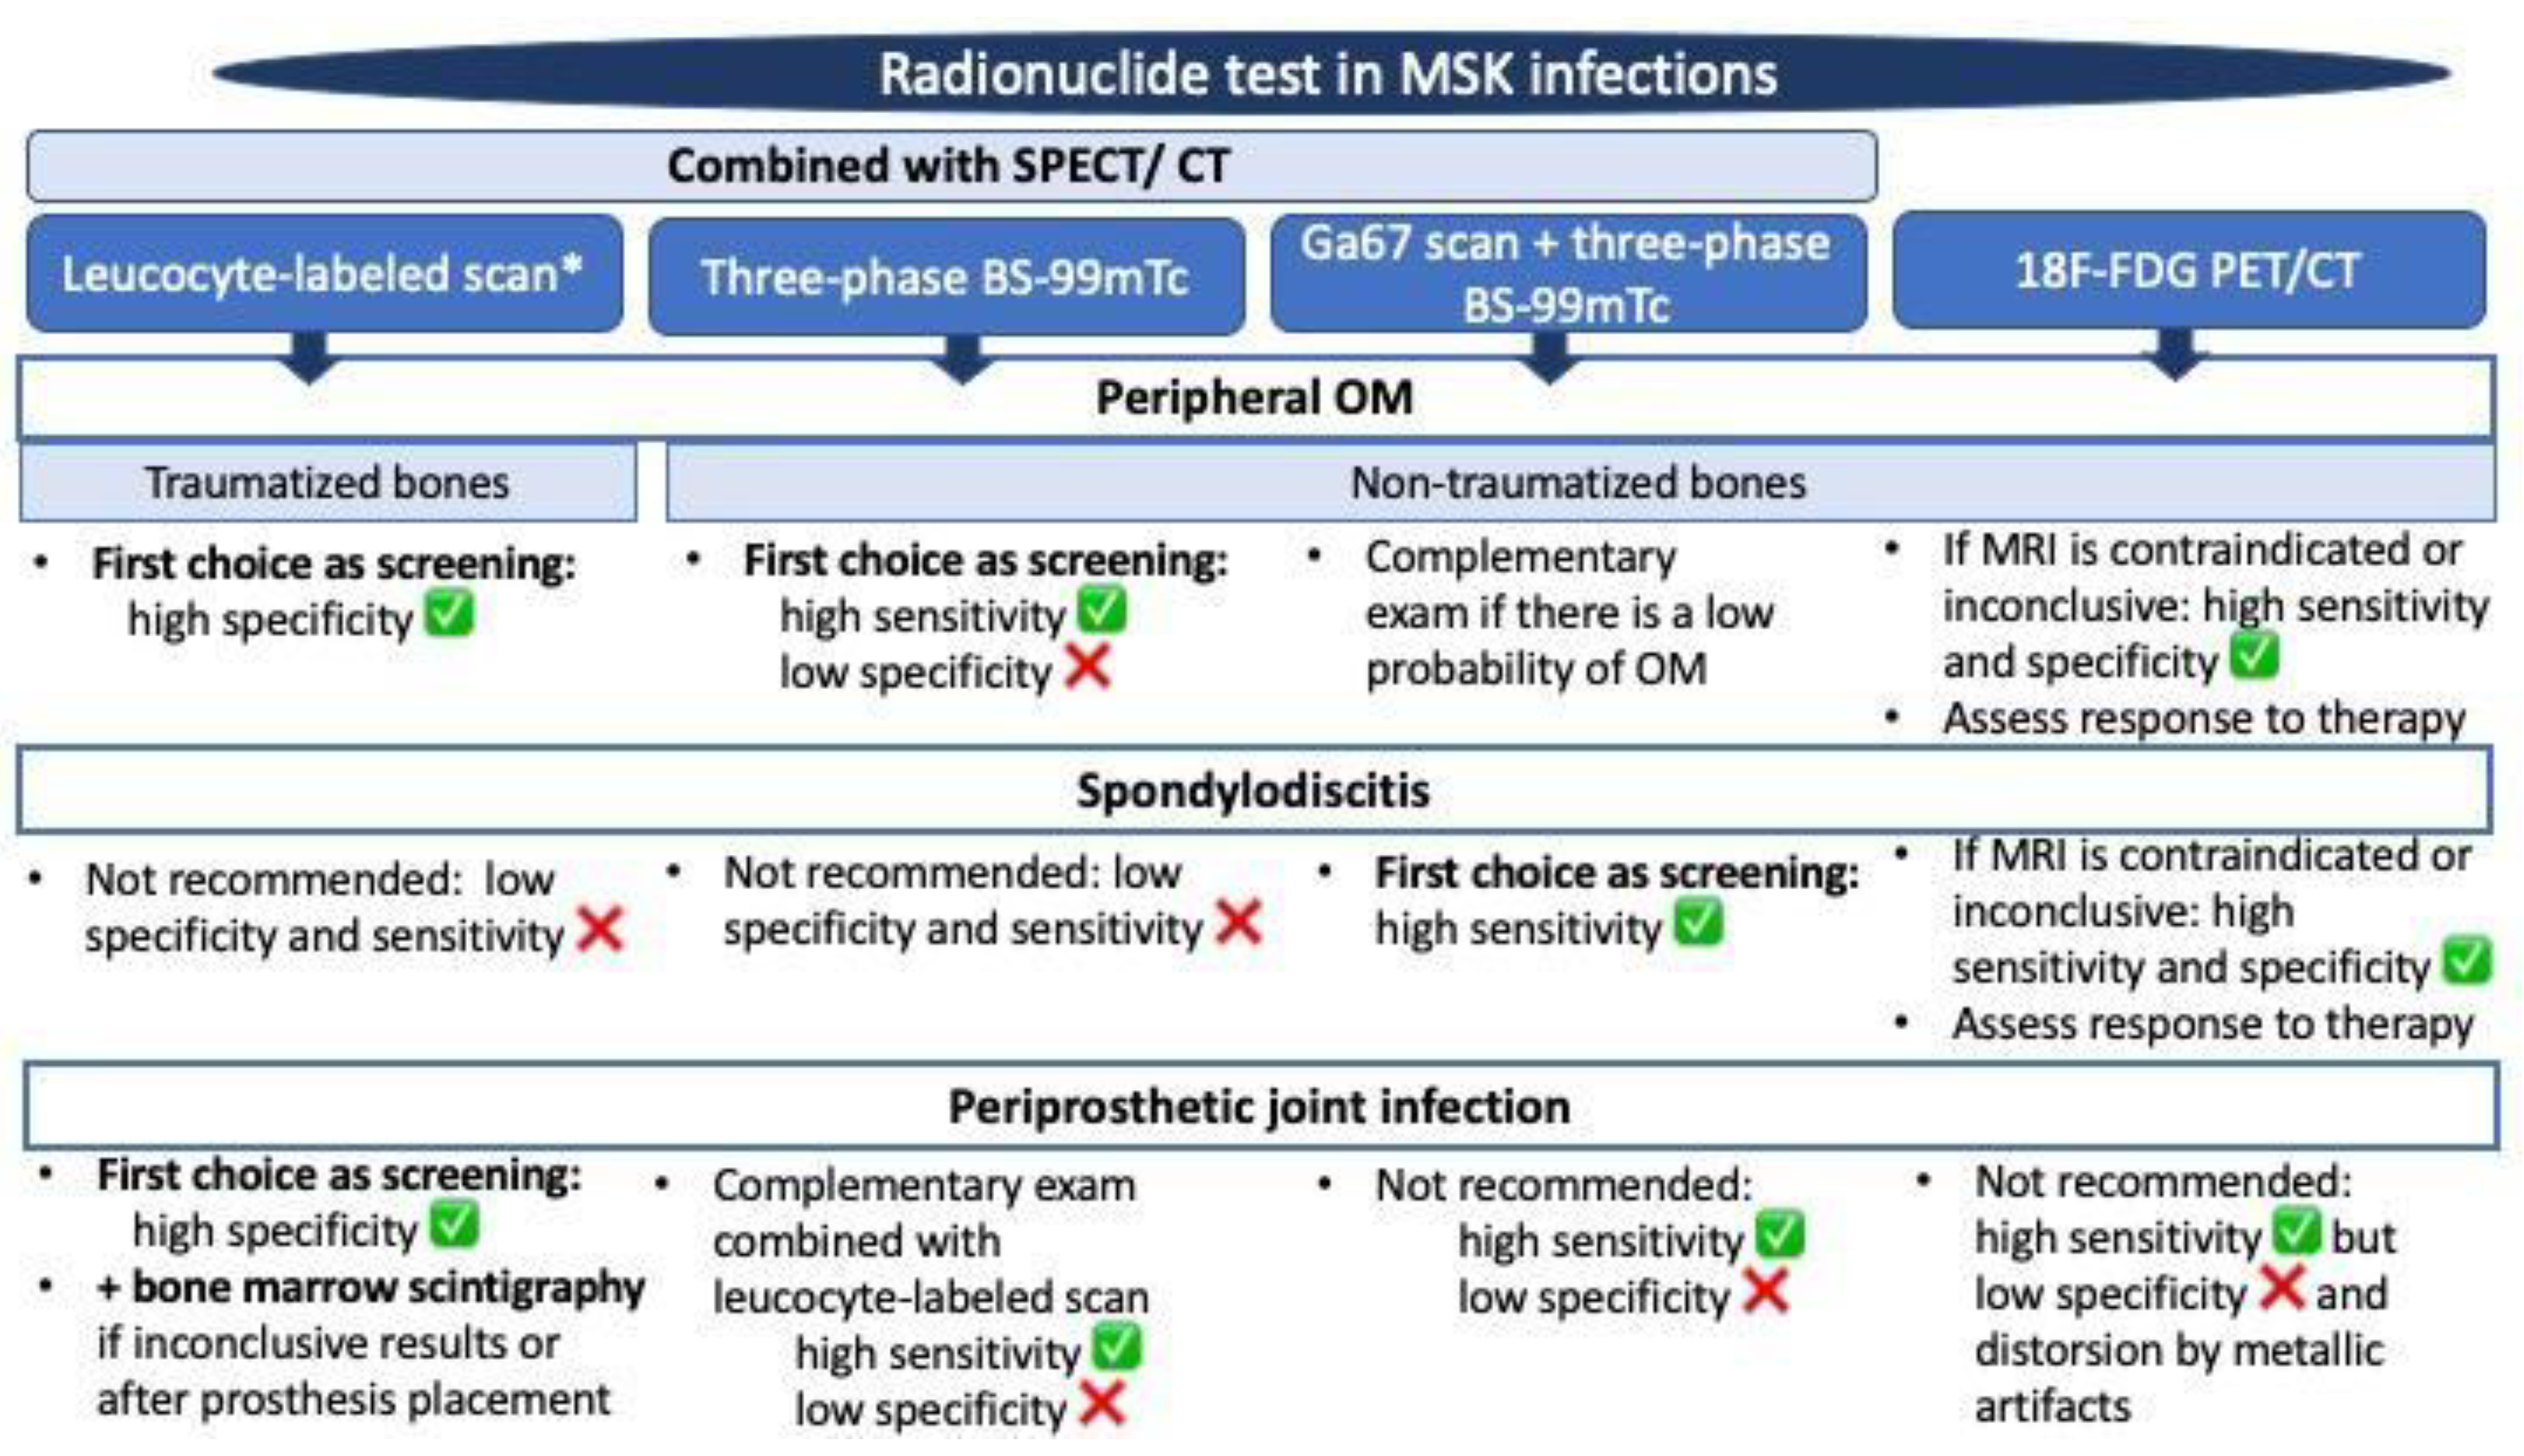

2. Fundamental Issues and Challenges Related to Conventional NM Techniques in Bone Infections

2.1. Bone Scintigraphy with Technetium-99m

2.2. Bone Scintigraphy with Gallium Citrate (Ga-67)

2.3. In Vitro and In Vivo Labeled Leukocyte Bone Scintigraphy

3. The Introduction of Hybrid NM Techniques in Bone Infections

3.1. SPECT/CT plus 99mTc, 67Ga or Labeled Leucocyte Scintigraphy

3.2. Fluorine-18-Fluorodeoxyglucose (18F-FDG) with Positron Emission Tomography (PET/CT)

4. Which Is the Most Appropriate Test for the Diagnosis of Bone Infections: Imaging, NM Scans, or Both?